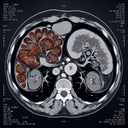

МРТ нирок

МРТ нирок (магнітно-резонансна томографія нирок) — це неінвазивний метод візуалізації, який використовує магнітні поля та радіохвилі для створення детальних зображень нирок та прилеглих структур. Ось основна інформація про МРТ нирок: ### Коли звертатися на МРТ нирок: 1. **Підозра на пухлини**: Якщо є підозра на наявність новоутворень у нирках...